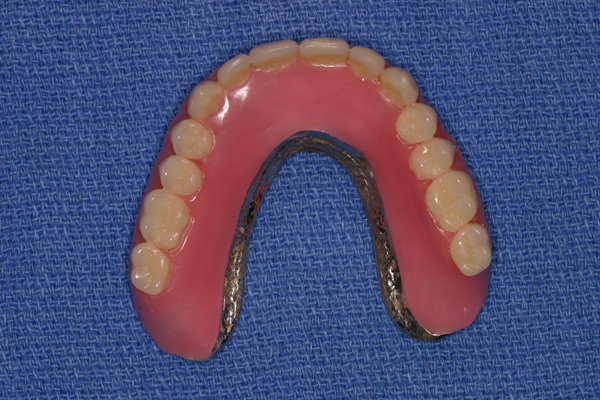

Problem: This patient comes in with badly broken-down teeth and periodontal disease. Her midline is off center. She wants something that will be anchored in so she can eat well and look fabulous.

Plan: Our plan… we removed the remaining teeth and placed four implants on the lower for a fixed/hybrid prosthesis. The upper required bone grafting and then placed eight implants that will support a connector bar prosthesis.

She is happy. We’re happy. Mission accomplished!